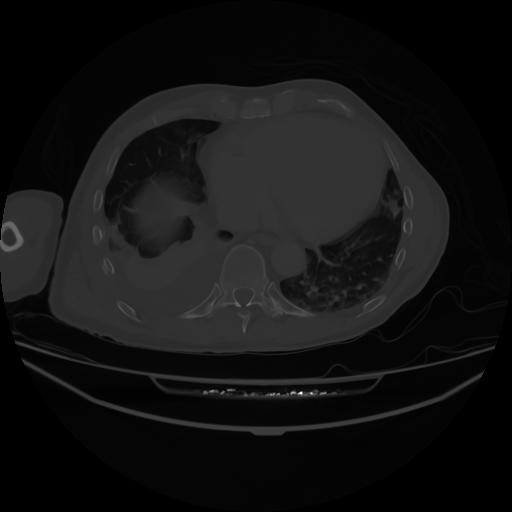

4 CUERPO,CE,Axial,3.0,CUERPO,,